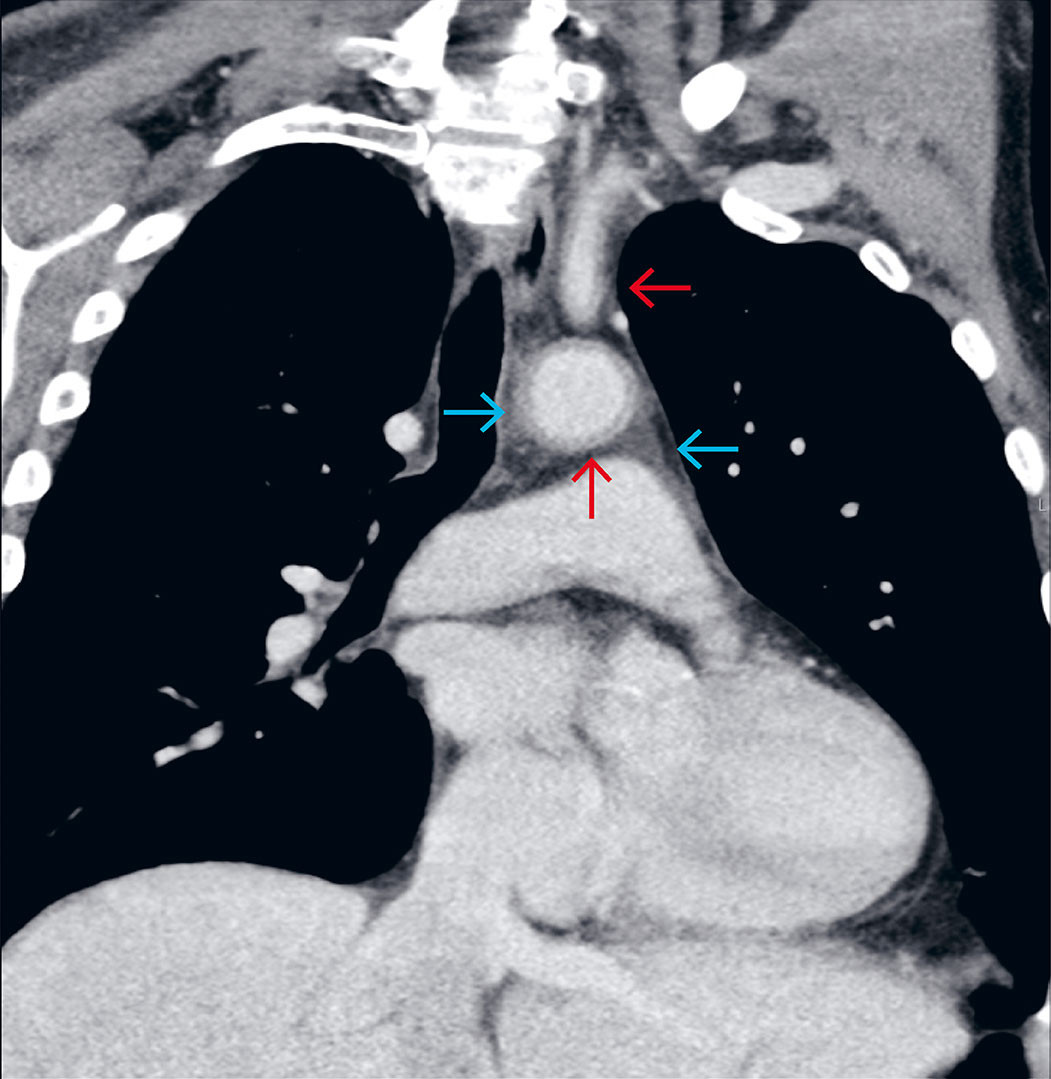

Due to a lack of response to treatment after three days, the antibiotics were changed to intravenous cefotaxime 2 g x 3, combined with metronidazole 1.5 g x 1. On day four, the treatment was again switched to intravenous meropenem 1 g x 3 and vancomycin 1 g x 2. CRP had risen to 331, and the patient was still experiencing fever spikes > 38.7 °C. He was also now reporting mild chest pain but was considered to have unusually few signs of infection. All cultures were negative, a chest X-ray was normal, and transthoracic echocardiography showed no signs of endocarditis. On day four, a contrast-enhanced computed tomography (CT) scan of the chest, abdomen and pelvis was performed, leading to the correct diagnosis. The CT scan revealed vasculitic changes in the aorta and several branch vessels (Figure 1). G-CSF-induced aortitis was considered the likely diagnosis, and after an interdisciplinary discussion, peroral treatment with prednisolone 40 mg x 1 was initiated. Over the next few days, the patient became afebrile, and CRP decreased significantly. Antibiotics were discontinued after seven days, and the patient was discharged in good health after ten days. Prednisolone was tapered and discontinued over the course of three months. The lymphoma was successfully treated with four R-CHOP cycles, followed by two cycles of rituximab monotherapy. G-CSF was not administered again after the first cycle. Two years after initiating treatment, there were still no signs of lymphoma or vasculitis relapse.

Imaging is crucial for diagnostics and preventing unnecessary antibiotic treatment. Ultimately, the CT scan with contrast in the portovenous phase led us to the correct diagnosis. For targeted investigations or follow-up of extracranial vasculitis, positron emission tomography with integrated CT (PET/CT) or magnetic resonance imaging (MRI) are more suitable modalities (10). Malignancy and large vessel vasculitis sometimes occur simultaneously, but this is more often a coincidence than a paraneoplastic phenomenon. True paraneoplastic vasculitis typically affects small and medium-sized vessels and is more common in hematologic cancers than in other types of cancer (11). Paraneoplasia cannot be ruled out in our patient, but we believe that G-CSF was most likely the trigger. Other diagnostic tests showed no evidence of an underlying rheumatic condition. Prednisolone was tapered relatively quickly compared to, for example, treatment for temporal arteritis. The role of corticosteroids in treating this condition remains unclear, and further research is needed to determine the most effective approach. In a systematic review article from 2021, with 49 reported cases of G-CSF-induced aortitis, no significant difference was found in the time from onset to remission with or without corticosteroid treatment (3). Discontinuation of G-CSF is important for achieving remission from vasculitis.